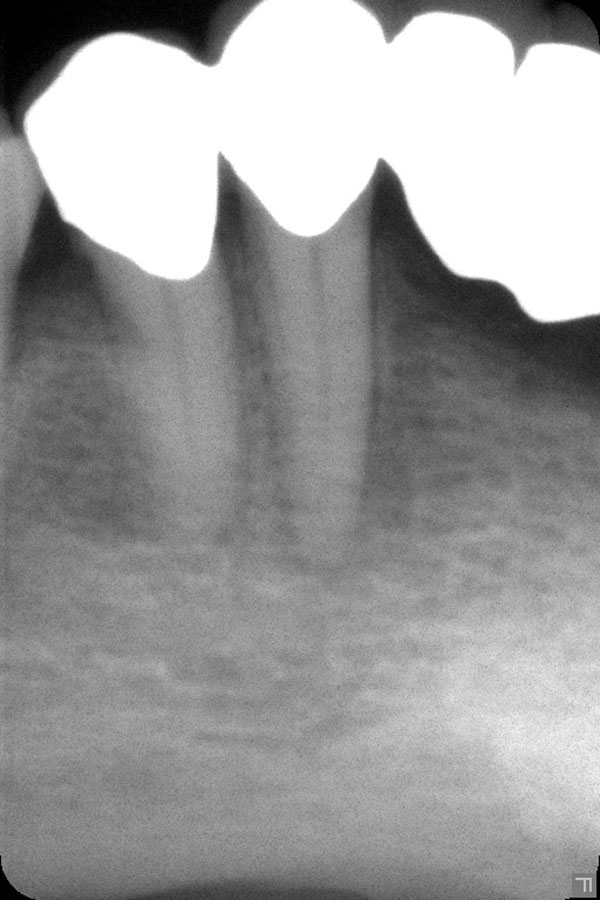

Im Röntgenbild ist deutlich eine ausgedehnte Transluzens im Sinne einer tiefen Zahnzwischenraumkaries (D4) sichtbar. Die Karies am Zahn 14 unter der Füllung wurde schon entfernt. Heute stand der Zahn 16 auf dem Plan – im Röntgenbild hell hervorgehoben:

Von außen fotografiert sieht der Zahn wieder weitgehend harmlos aus: